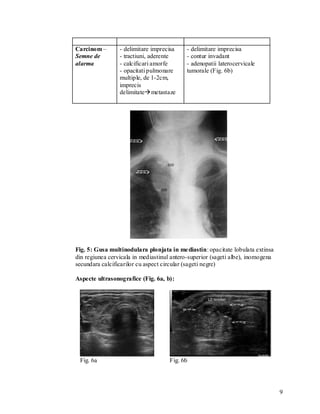

 Neoplazice

 Primare: limfoame, leucemii

 Limfoame Hodgkin : 85% au prezentare mediastinala sub forma

unei mase cu contururi convexe, lineare, cu aspect asimetric, cu

delimitare imprecisa spre parenchimul pulmonar (infiltrare

pulmonara sub forma unor “limbi de flacari”) (Fig. 14a)

 Limfoame non-Hodgkin: doar 20% au prezentare mediastinala,

sub forma unei mase policiclice, cu aspect simetric (infiltrare

pulmonara rara) (Fig. 14b)

 Caracteristic: aparitia calcificarilor ganglionare post chimio- si

radio-terapie

Fig.14a                                     Fig.14b

Fig. 14 Adenopatii tumorale (sageti): a. Rx torace – Limfom Hodgkin. b. Tomografie

plana – Limfom Non-Hodgkin